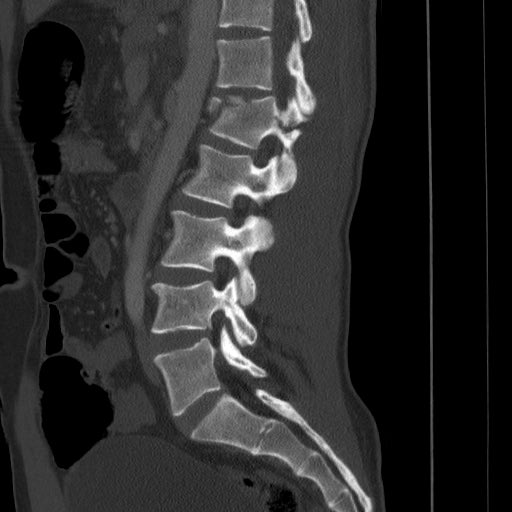

Fractured spine

Fractured spine 140 фотографий